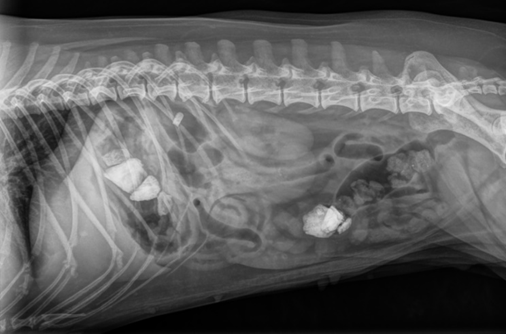

Tapausselostus: Vierasesine suolistossa

Koirat

Röntgen ja ultraääni